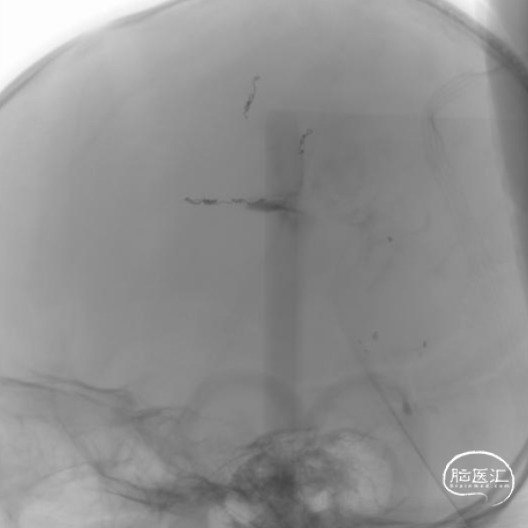

本例患者术前脑血管造影提示瘤体主要由双侧大脑前动脉终末分支供血,造影静脉期瘤体显影明显,因此我们选择先采用神经介入技术超选部分主要供瘤动脉予弹簧圈栓塞,减少瘤体的供血。之后再行开颅探查双侧额顶叶占位性病变切除术。